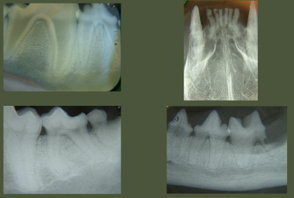

What are these 4 images?

Why do we take radiographs?

What is going on in these four images?